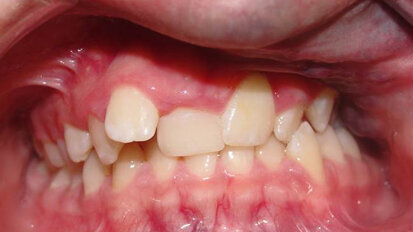

Avulsion in Paediatric Dentistry: Management of a Double Dental Emergency in a Child

General dental practitioners and paediatric dentists face real dental emergencies that effect children, especially dental trauma. Avulsion is considered, in...